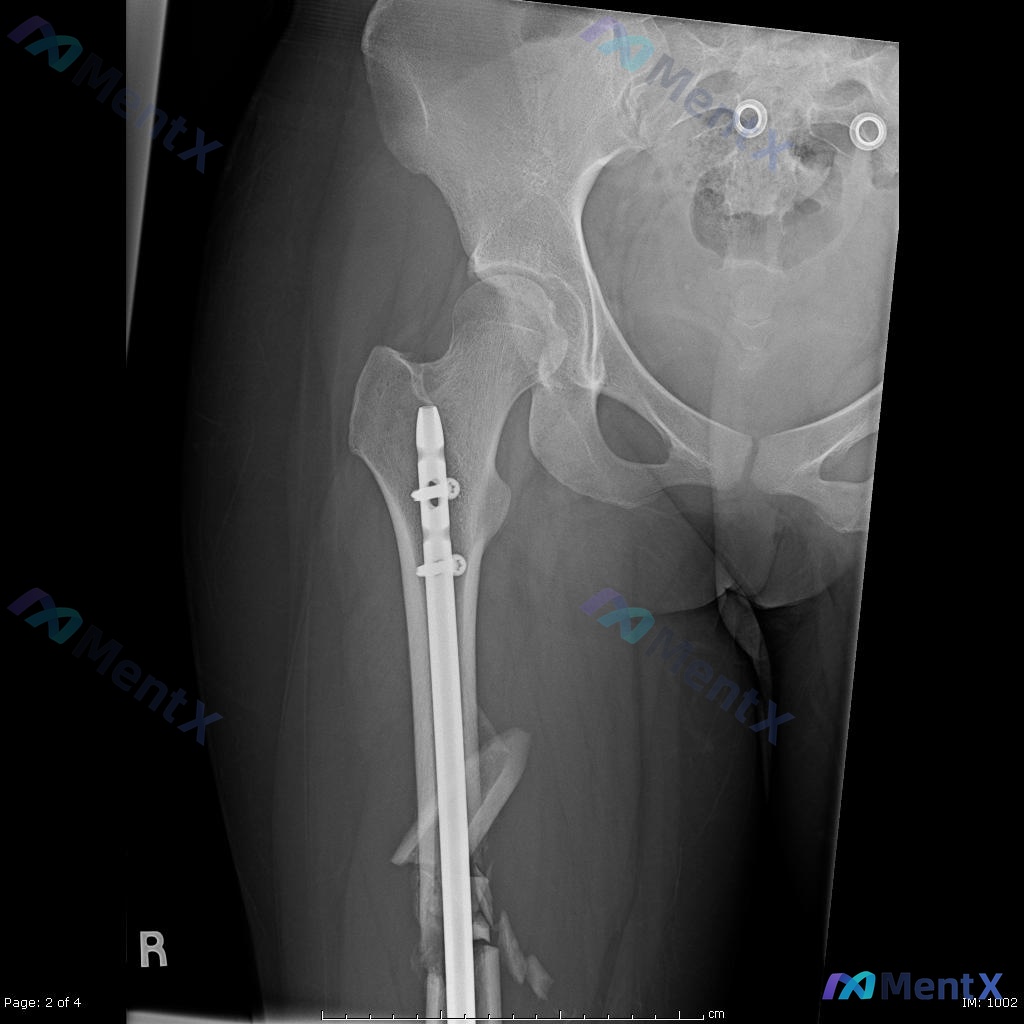

- 术后(图C/D):已行12mm髓内钉内固定(从大转子插至膝关节上方),远端两枚横向锁钉固定;内固定物形态完整、位置良好;骨折端大致对位,粉碎骨块被髓内钉包容